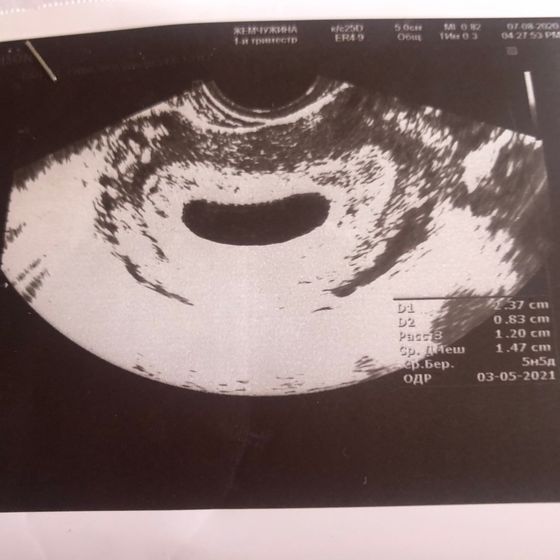

У вас нет желточного мешочка. Посмотрите на фото.

По фото узи видно что желточного мешочка нет! К сожалению это 99% анэмбриония!!

Не написан его размер, значит его нет, и по фото на узи видно пустое плодное яйцо, должно быть плодное яйцо и внутри ещё одно не большое, а у вас пустое

У девушки срок 5 недель эмбриональный, по месячным 8 недель уже, это уже 100% должен быть желточный мешочек хотя бы, а у неё просто пустое плодное яйцо(( к сожалению так бывает